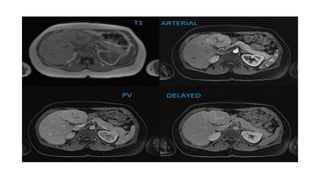

• Classic HCC …CT or MR imaging is a mass that shows

1. APHE

2. subsequent washout during PVP or more delayed images,

and

3. delayed capsular or pseudocapsular enhancement

• When present, these 3 major features allow HCC to be

treated without the need for biopsy confirmation

• Tumor thrombus may show arterial phase enhancement

• CT sensitivity 67.5% Specificity 92.5%

• MRI sensitivity 80.6% and specificity 84.8%